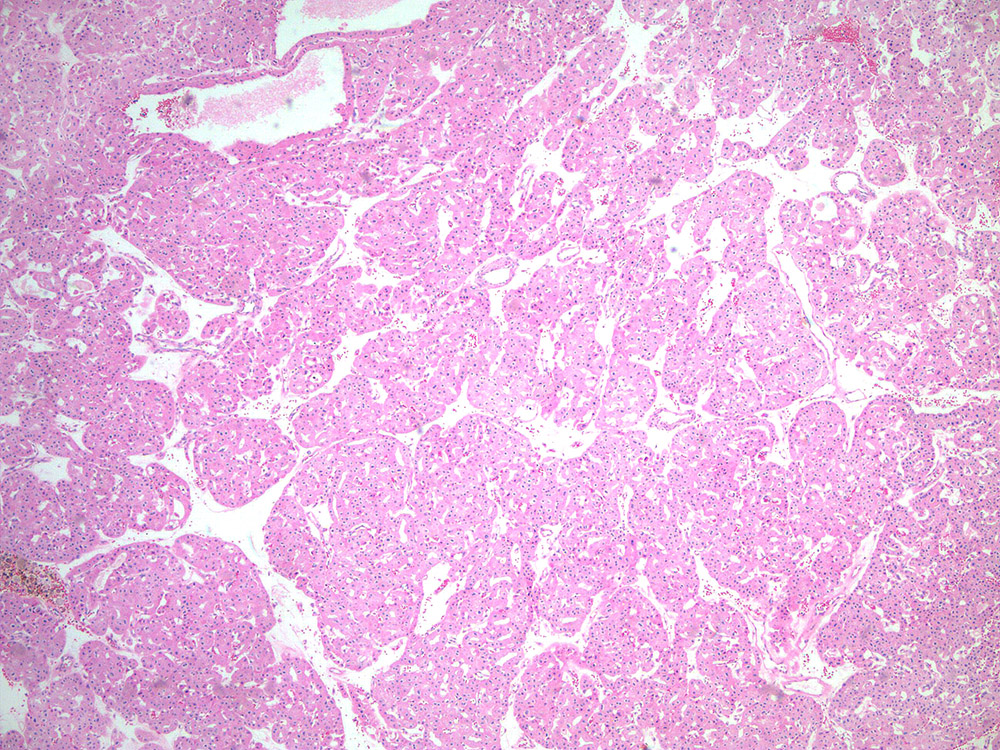

chromophobe RCC |

chromophobe |

Case description (by case creator):

Renal mass- 57 year old man